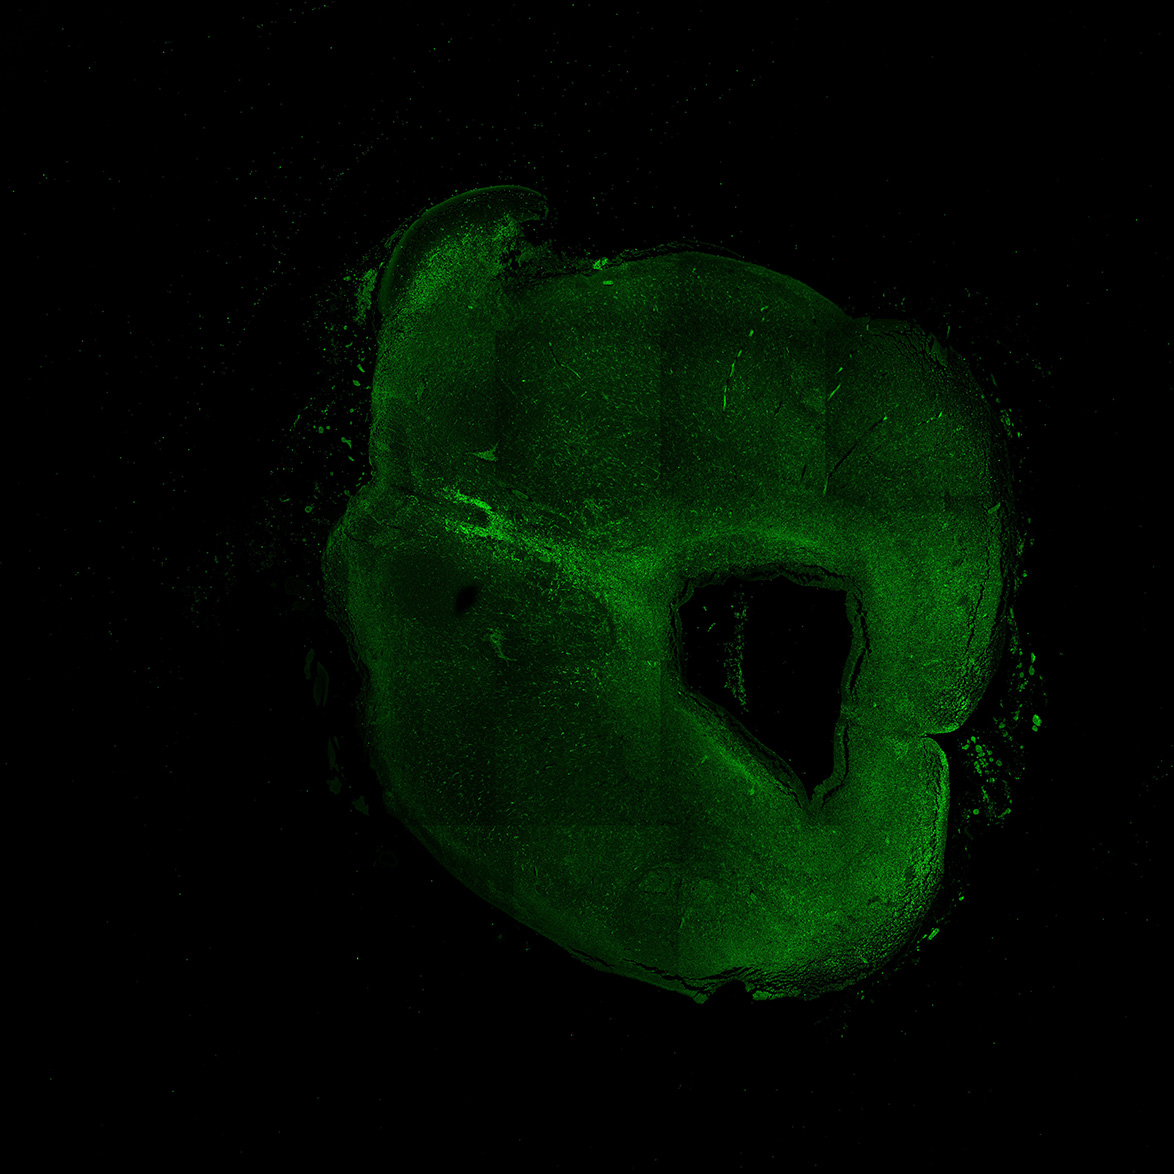

An anatomical analysis of the developing human midbrain from 6 post-conceptional weeks (PCW) to 22 PCW reveals increased tissue complexity, characterized by the emergence of dopaminergic nuclei, as highlighted by immunofluorescence analysis for tyrosine hydroxylase (TH).

6PCW

6PCW human midbrain